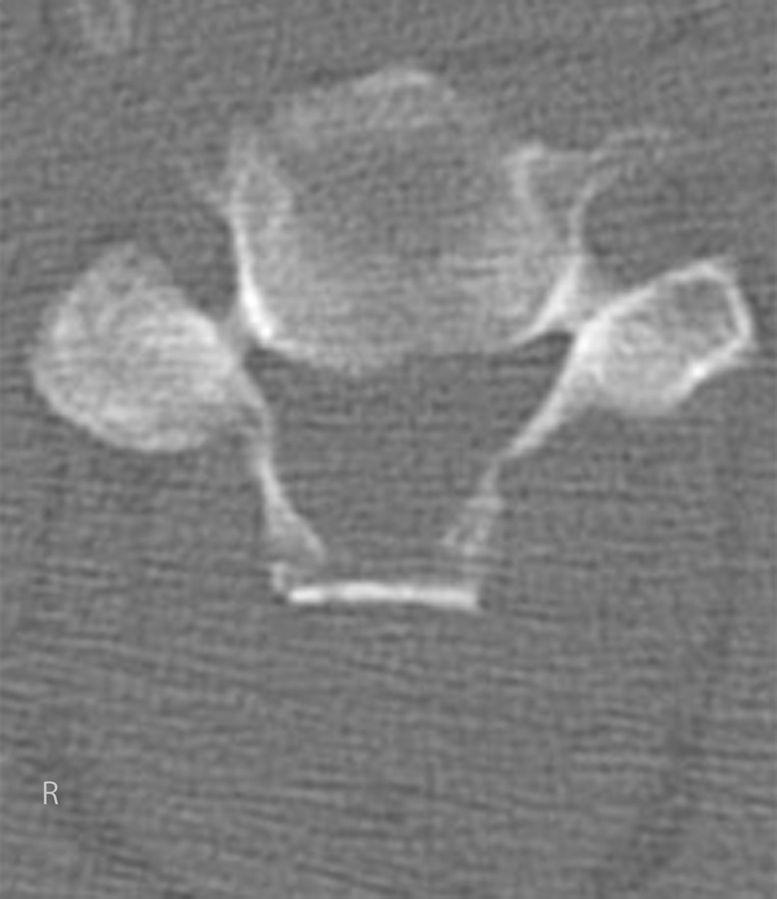

STEP 3 CREATE GROOVES: Cut the center of each lamina and create bilateral grooves using a high-speed burr.

步骤3制作沟槽:在每个椎板中央切割,并用高速磨钻制作双侧沟槽。